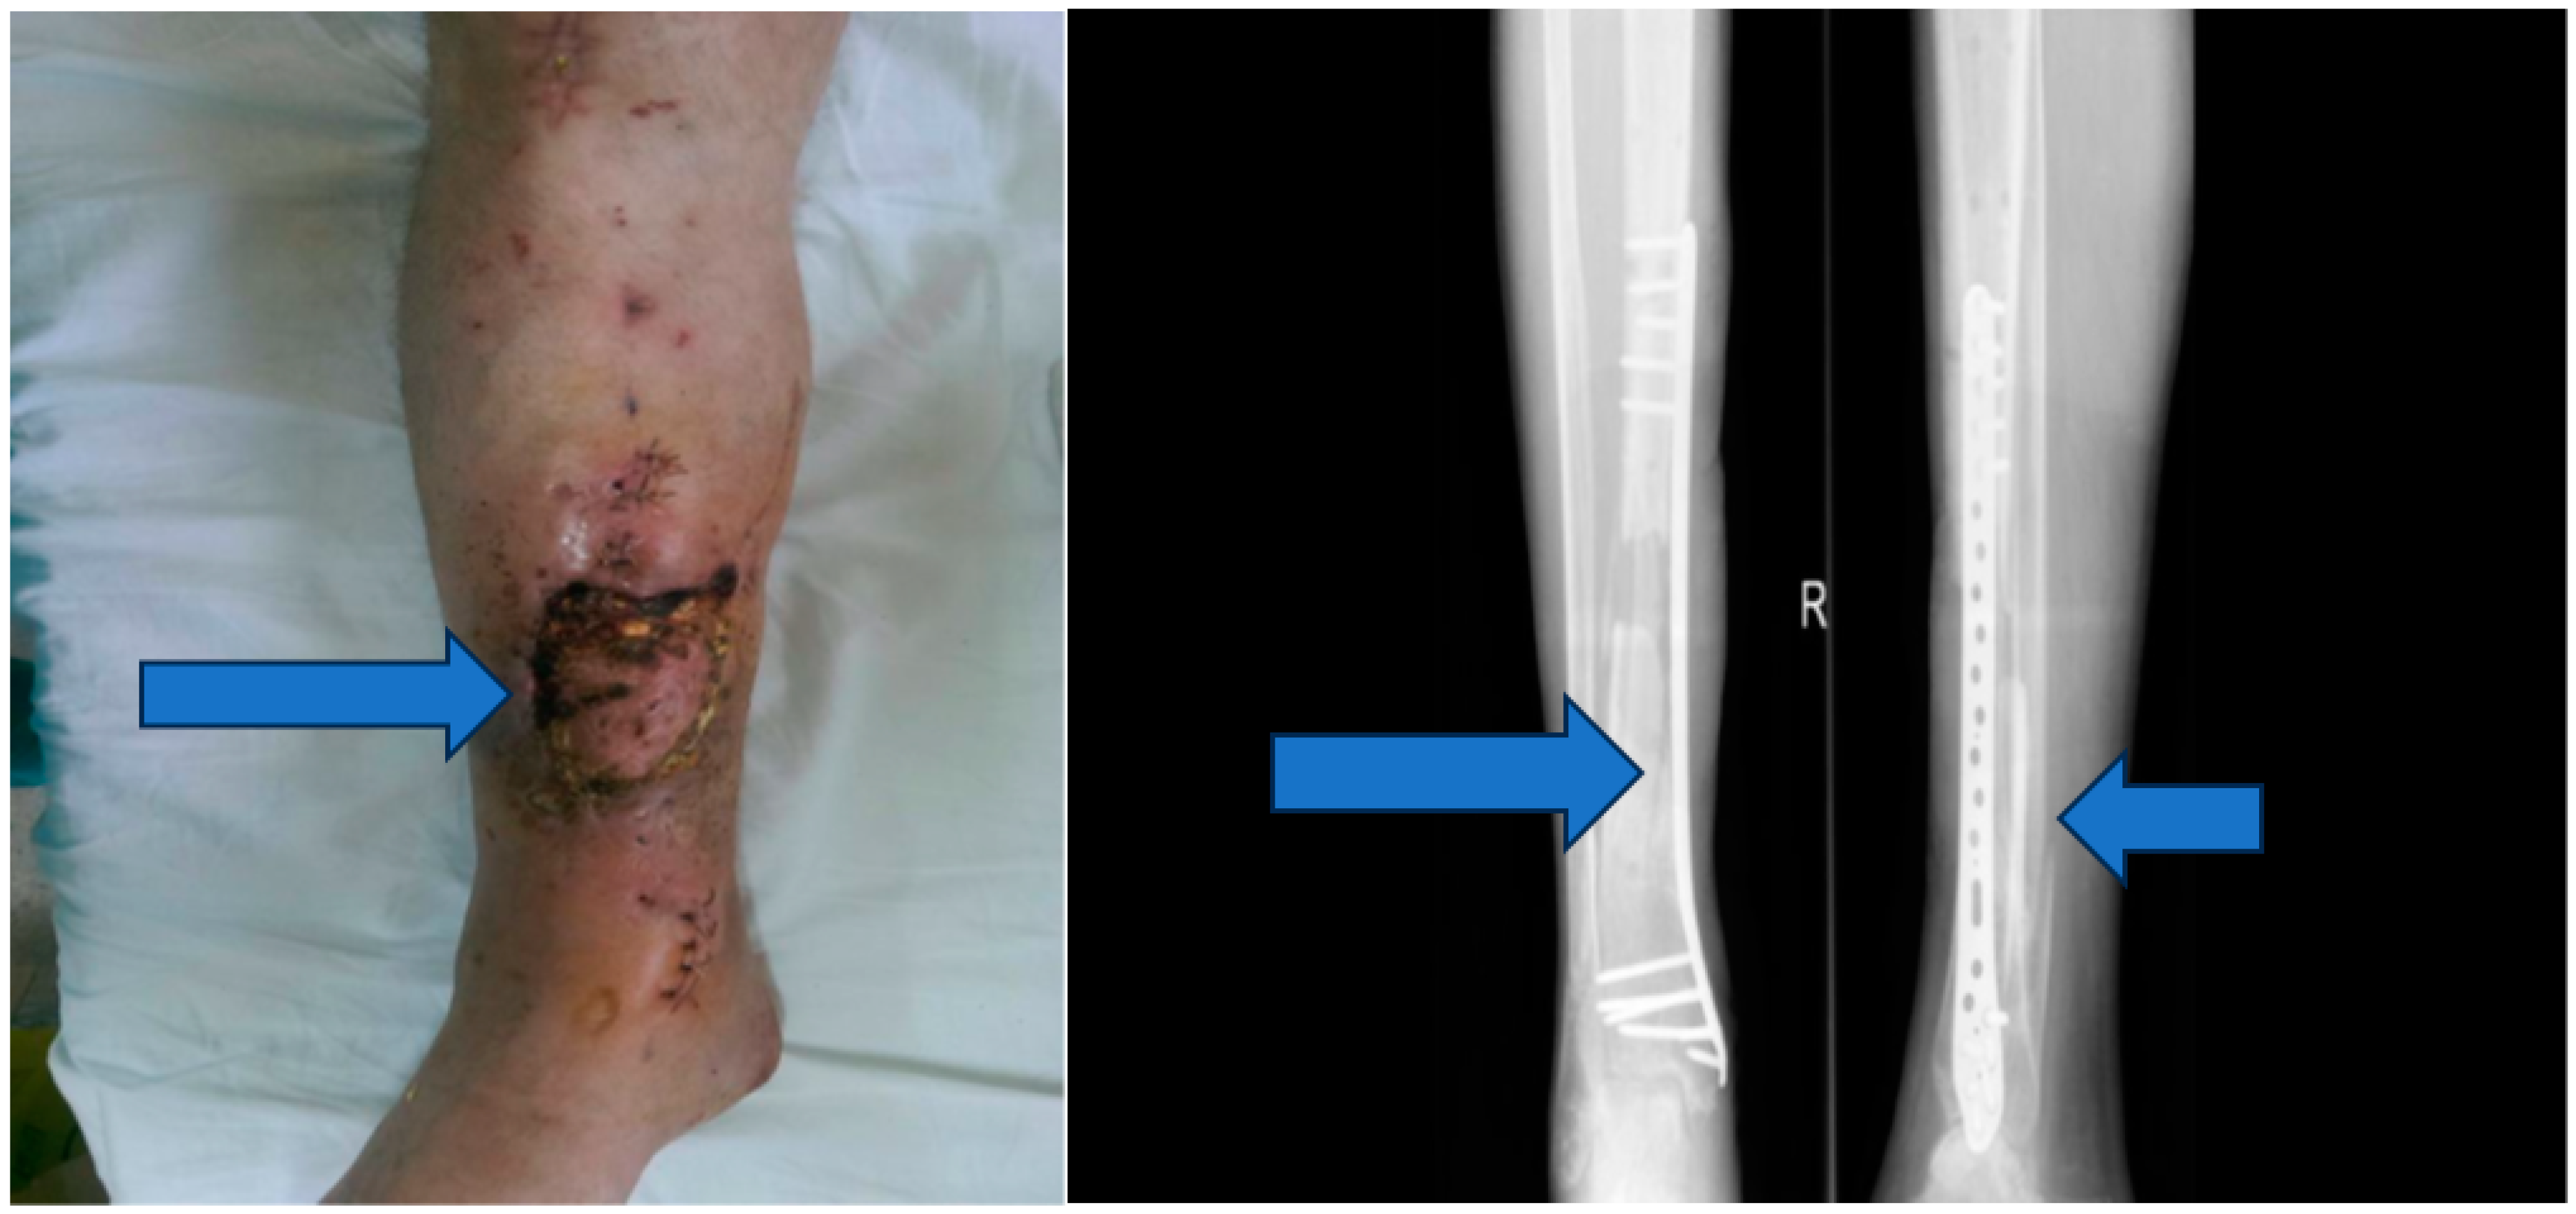

2.4. Clinical Assessment and Follow-Up

Throughout the treatment, the patient’s progress was closely monitored, and clinical signs of healing were recorded. Sterile cultures were obtained to verify the resolution of the infection. The patient’s overall condition, pain level, and functional status were assessed at regular intervals (Figure 7).

Figure 7. Six-month follow-up.